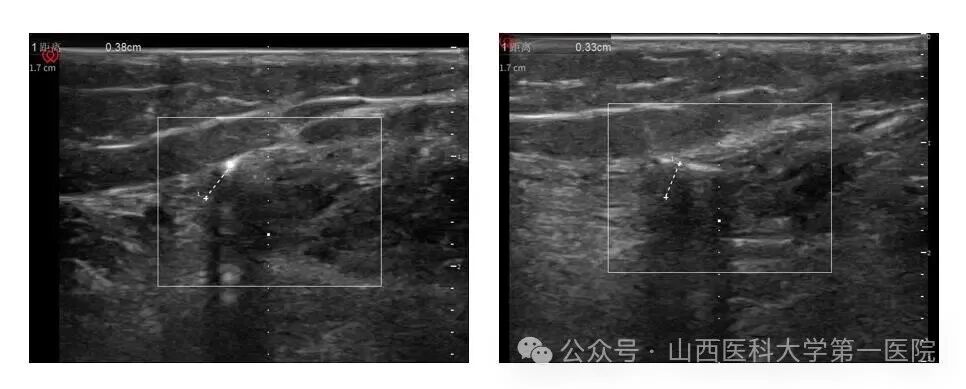

12月16日,山西医科大学第一医院泌尿外科任力娟副主任医师团队运用国际领先的微创技术,为长期饱受难治性膀胱过度活动症折磨的患者武女士成功实施了山西省首例创伤最小的胫神经刺激器植入术,在局部麻醉下通过长约0.5厘米的微小切口,以0.2厘米的精准距离刺激胫神经,术中刺激应答良好,整个手术过程用时约15分钟。

任力娟介绍到,本次手术在科室主任曹晓明和手术室护士长田华的精心安排下,在麻醉科副主任医师井子夜精准超声定位以及手术室吴琼、王钟皎两位护士协助下顺利完成;植入式胫神经刺激疗法通过精确定位,将微型刺激器植入踝关节胫神经附近,创伤极小、手术时间短,为开展日间手术提供了有力支撑,具有显著优势和技术突破性,希望该疗法能早日通过临床试验,惠及更多尿失禁患者。未来团队将持续优化方案,力争让90%符合适应症的患者实现“当天手术、次日恢复正常生活”的目标。”